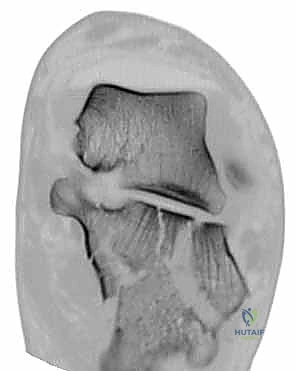

- الأشعة المقطعية (CT Scan): وهي الخطوة الأهم والأكثر حيوية. توفر الأشعة المقطعية صوراً ثلاثية الأبعاد وتقاطعاً دقيقاً للكسر، مما يسمح بتصنيف الكسر (نظام ساندرز - Sanders Classification) وتحديد عدد الشظايا العظمية ومدى انزياحها داخل المفصل. بناءً على هذه الأشعة، يضع الدكتور هطيف خطته الجراحية الدقيقة.

3. كشف الكسر وإعادة البناء (Reduction)

بمجرد كشف العظم، يتم تنظيف التجمع الدموي. يقوم الجراح بكشف السطح المفصلي المكسور. باستخدام أدوات دقيقة، يتم رفع الشظايا العظمية المنخسفة إلى مكانها التشريحي الأصلي. يتم استعادة ارتفاع وعرض العظم، والأهم من ذلك، استعادة السلاسة التامة لسطح المفصل.

توضح الصور التالية مدى تعقيد الجراحة والدقة التي يتطلبها تثبيت عظم الكعب، والتي يعكسها التميز الجراحي للأستاذ الدكتور محمد هطيف: